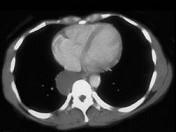

问题 男,42岁,轻度咳嗽,胸部隐痛2月余,请结合CT检查,选出最可能的诊断 ( )

选项 A.食管囊肿 B.淋巴管囊肿 C.淋巴管瘤 D.支气管囊肿 E.神经源性肿瘤

答案 D